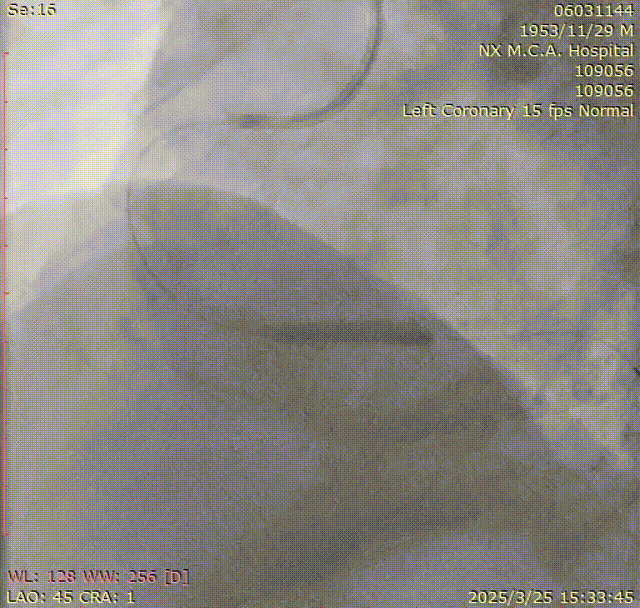

LAD近中段原支架通畅未见明显狭窄

LCX粥样硬化

RCA近中段粥样硬化,远段弥漫性病变并可见钙化影,后三叉前狭窄80-90%